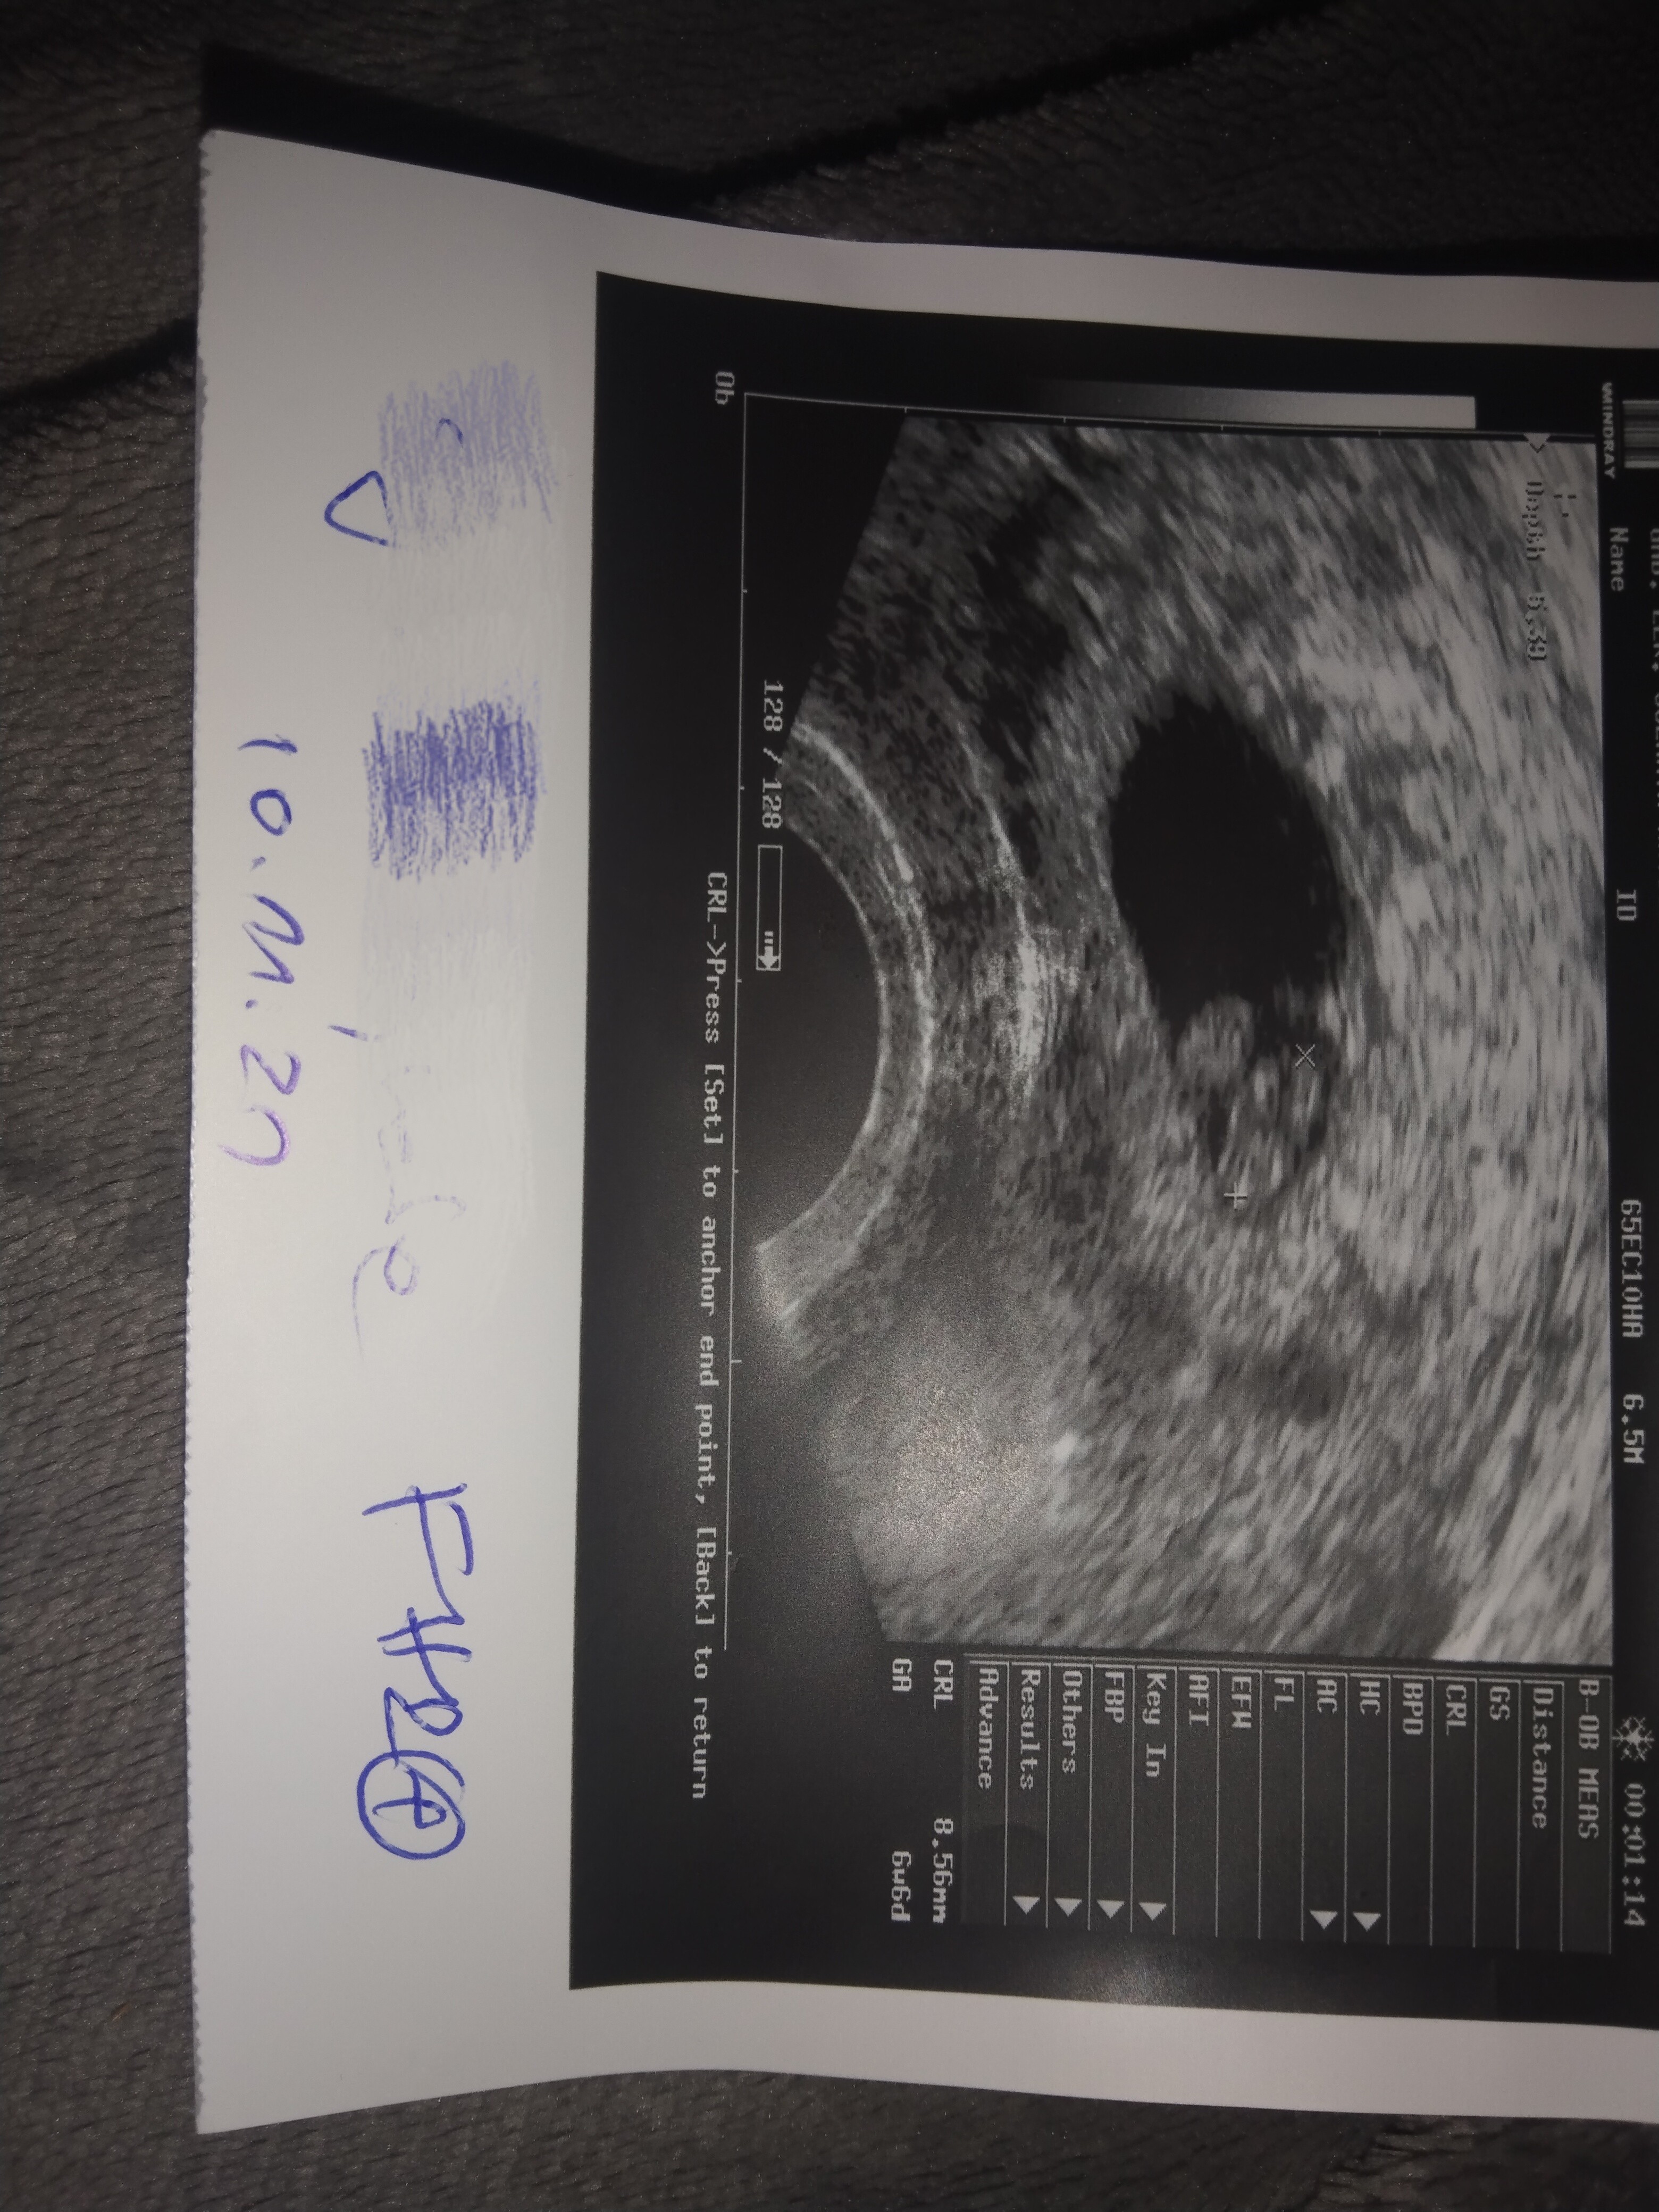

Ciekawe bo z moich obliczeń wynika że 27 października powinna być w 5 tygodniu ciąży i to się pokrywa z usg z współżycia 23 września. Z waszego na usg powinien być wtedy 4 tydzień niecały. To samo wizyta 10 listopada 6 i 6 tydzień to wychodzi z 23 września a z waszego 6 tydzień dopiero. Tylko test ci da 100 % odpowiedź. Ciąża to tez nie matematyka a usg tez może być nie dokładne wiec nikt ci nie powie czyje to dziecko. Bo nie wiemy kiedy partnerka miała owulacje.

Właśnie na USG datę ostatniej miesiączki której nie było ma wpisywane GA 5w0d. To było z USG 27 października

To jest jej pierwsze USG